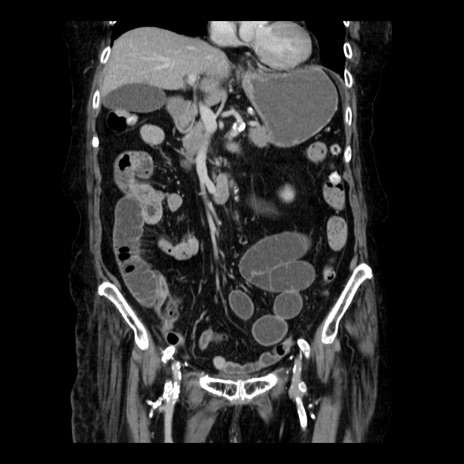

症例14(冠状断像)

【症例】 90歳代女性

【主訴】 腹痛・嘔吐

【現病歴】今朝から左側腹部痛を認めた。 経過観察していたが、嘔吐を認めたため来院。

【既往歴】 子宮癌術後

【身体所見】 意識清明、BP 127/54mmHg、P 98bpm Sp02 95%(RA)、BT 35.8°C、腹部平坦・軟腸ぜん動音聴取良好、右下腹部圧痛(+) 反跳痛なし

【データ】WBC 9800、CRP 0.46

横断像